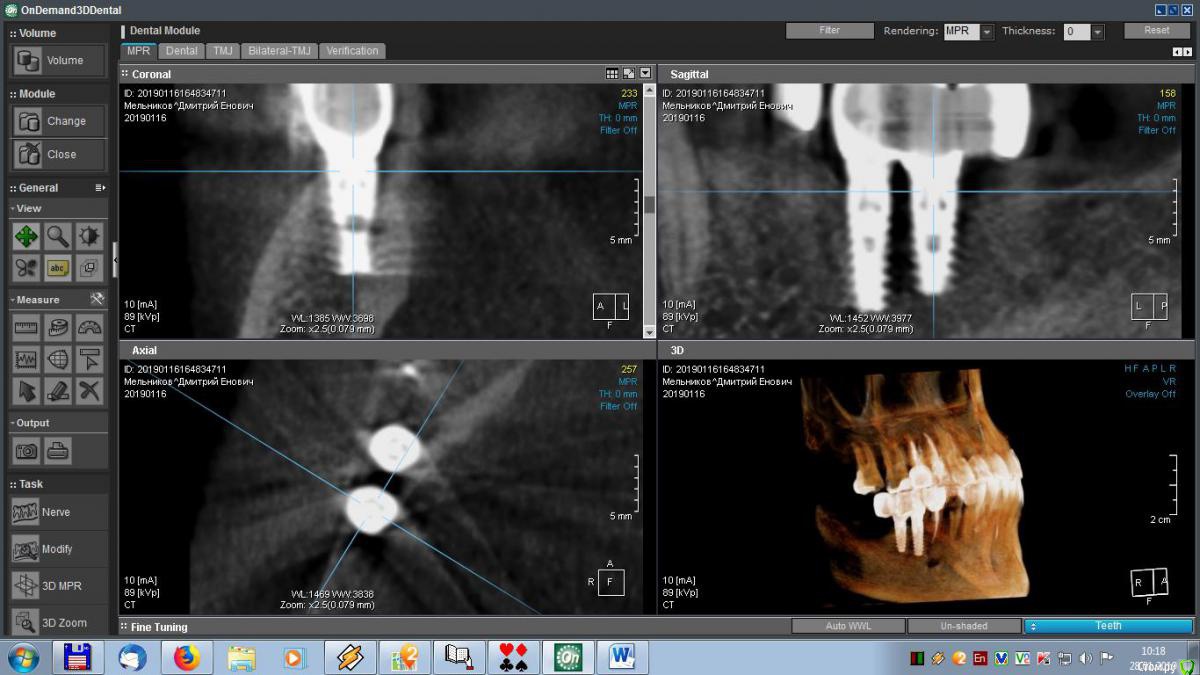

meld Опубликовано 29 января, 2019 Автор Поделиться Опубликовано 29 января, 2019 Здравствуйте, уважаемые доктора! Скоро год, как мне поставили метало-керамические коронки. До сих пор я ощущаю зуд в области имплантатов. На контрольном приеме врач ничего криминального не увидел, прописал чистку, фотосан и КТ, Я все сделал, по КТ врач сказал, что все нормально. Посмотрите, пожалуйста, мои среза и подтвердите (или нет) - все ли нормально. Спасибо. Ссылка на комментарий

meld Опубликовано 29 января, 2019 Автор Поделиться Опубликовано 29 января, 2019 Выложил больше срезов. Спасибо. Ссылка на комментарий